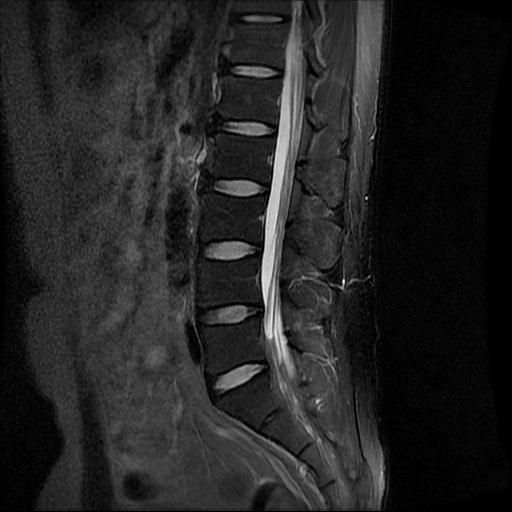

허리 MRI 전문가분들 의견부탁드립니다.

이번에 허리 MRI찍었는데

상태 어떤지 고견 여쭙습니다.

• 3번 째 사진

큰 이상이나 문제점은 없어 보이는 것으로 생각되는데요, 허리통증이 지속되는 경우에는 반드시 디스크 질환에 의한것은 아닐 수 있습니다.

현재로썬 디스크 상태는 심하지않는것으로 확인이 됩니다.